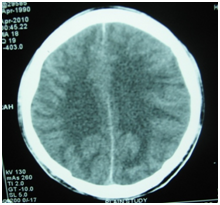

Imaging is required to rule out concomitant intracranial complications, or evidence of increased intracranial pressure. CT scan may show ventricular dilatation (Figure 10). In cases of otitic hydrocephalus, an MRI and magnetic resonance venogram should be performed to evaluate for ventricular enlargement, or coexisting intracranial complications, such as significant sinus thrombosis with obstruction. Magnetic resonance venogram will also confirm the presence of lateral sinus thrombosis, but is not required to make a diagnosis of otitic hydrocephalus.

Figure 10 CT scan showing dilated ventricles.